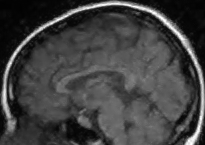

To simulate various input noise levels, several values for have been selected in the range . The set of high-quality magnitude MR test images used is shown in Fig. 6, and may be obtained from http://bigwww.epfl.ch/luisier/MRIdenoising/TestImages.zip.

V-C Denoising of a magnitude MR knee image

We have also applied our CURE-LET denoising algorithms to an actual magnitude MR image of the knee. This 16-bit raw image has been acquired on a Siemens 1.5 Tesla Magnetom Sonata MR system, following a sagittal T2-weighted protocol. The standard deviation of the complex Gaussian noise has been estimated from a signal-free region of the squared data, as , and subsequently treated as known.

Fig. 11 shows the denoising results of the various CURE-LET algorithms. As observed, the noise is efficiently attenuated and the contrast is significantly improved, owing to a proper reduction of the signal-dependent bias introduced by the noise.